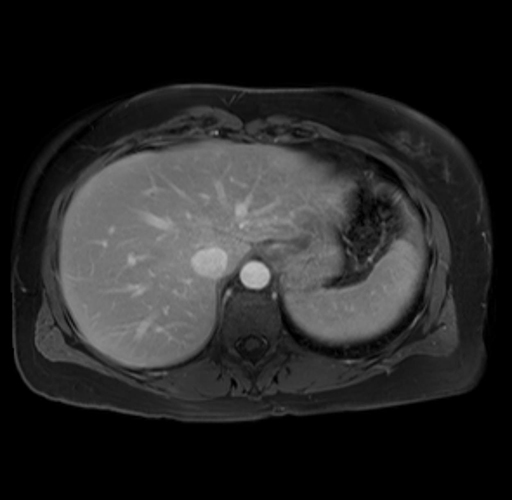

Imaging Analysis

Look through the patient's CT scan to identify any areas of concern for the necessary procedure.

Based on your CT findings, which issue(s) are present and would give reason for "planned slowing down moment(s)" in this case?

Considering a standard distal pancreatectomy procedure, what step(s) of the operation would you do differently in this case?